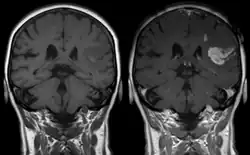

As first postulated by Harvey Cushing, raised intracranial pressure is the primary cause of the Cushing reflex.[3] Furthermore, continued moderate increases in cranial pressure allows for the Cushing reflex to occur. In contrast, rapid and dramatic pressure rises do not allow for the mechanism of the reflex to sufficiently take place.[12] Elevated intracranial pressure can result from numerous pathways of brain impairment, including: subarachnoid hemorrhages, ischemia, meningitis, trauma, including concussions, hypoxia, tumors, and stroke. In one study, it was confirmed that raised ICP due to subarachnoid hemorrhaging causes mechanical distortion of the brainstem, specifically the medulla. Due to the mechanism of the Cushing reflex, brainstem distortion is then swiftly followed by sympathetic nervous system over activity.[13] In addition, during typical neurosurgical procedures on patients, especially those involving neuroendoscopic techniques, frequent washing of the ventricles have been known to cause high intracranial pressure.[7] The Cushing reflex can also result from low CPP, specifically below 15 mmHg.[14] CPP normally falls between 70-90 mmHg in an adult human, and 60-90 mmHg in children.